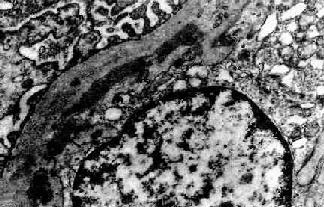

图12-8 毛细血管内增生性肾小球肾炎

电镜下见肾小球毛细血管基底膜表面上皮细胞下有多数驼峰状电子致密沉积物